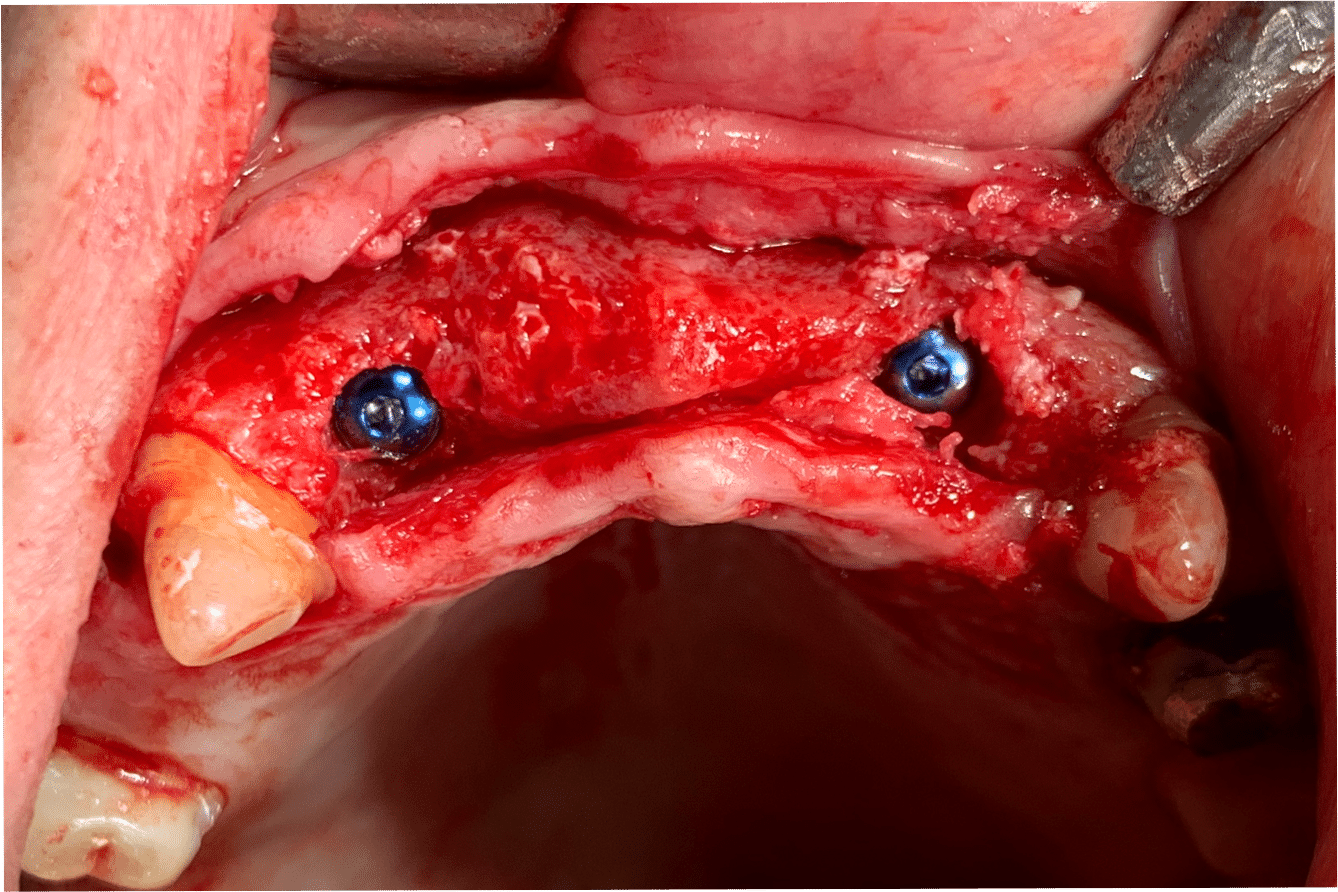

Implanturile vor fi inserate cu ghid chirurgical după 6 luni. Se vor insera implanturi în pozițiile 12, 22, 16, 36, 46.

S-a realizat scanarea digitală a arcadelor și ocluzia pacientului, iar împreună cu tehnicianul radiolog de la DigiRay, Dr. Eliza Drăgan a efectuat în software-ul 3Shape suprapunerea fișierului .stl al amprentei digitale peste fișierul .dcm de la CBCT. Medicul a planificat individual poziția și axul de inserție al fiecărui implant.